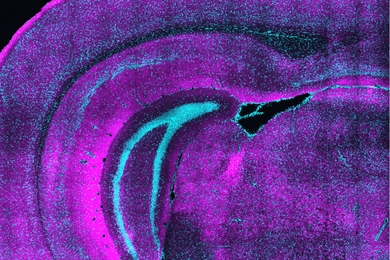

An international collaboration of neuroscientists, including MIT Professor Ila Fiete, developed a brain-wide map of decision-making at cellular resolution in mice.